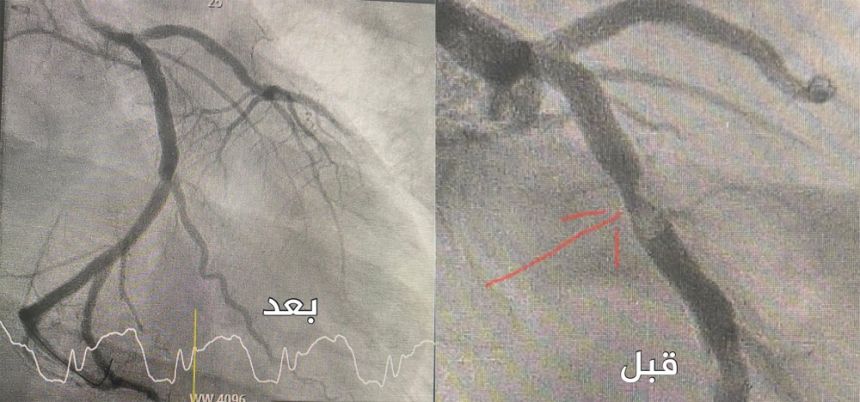

وأوضح تجمع القصيم الصحي أن الشاب الذي راجع المركز، كان يشكو من حدوث نوبات متكررة وآلام صدرية وضيق في التنفس، وتبيّن بعد خضوع المريض للفحوصات اللازمة إصابته بتضيق شديد وتكلس في الصمام الأورطي بسبب وجود تشّوه ولادي في الصمام (صمام ثنائي الشرف).